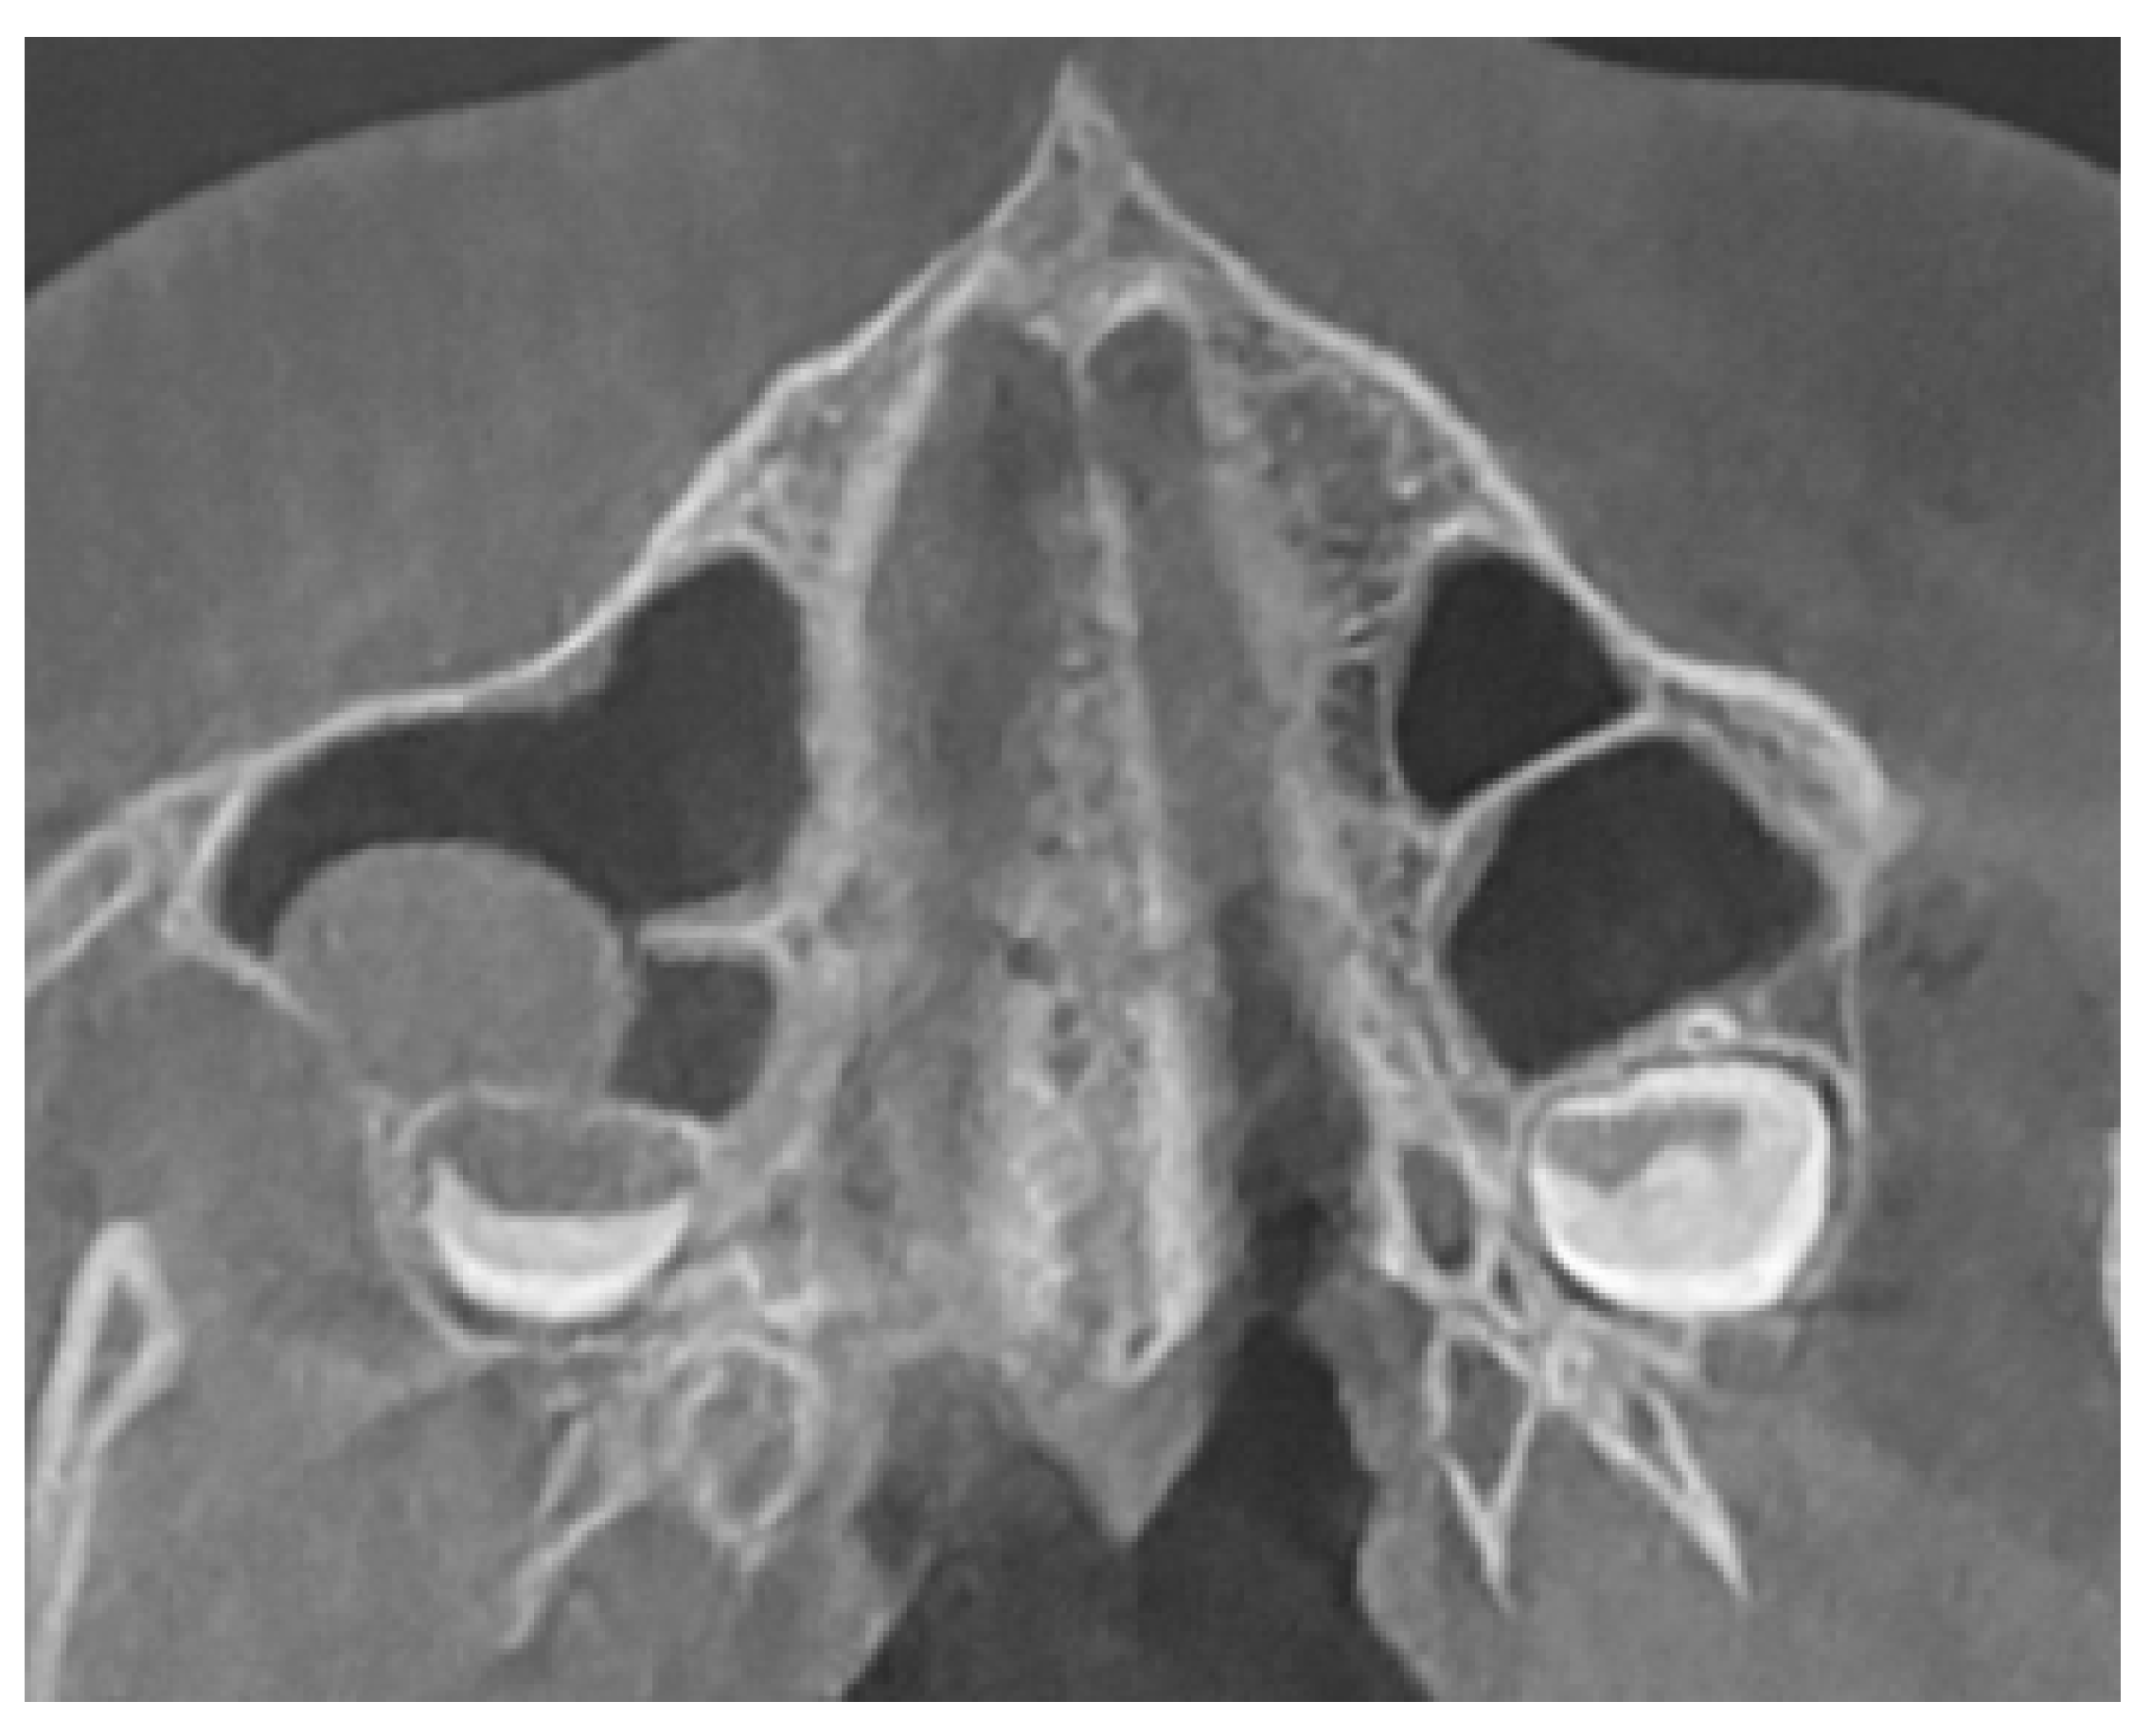

2.3. Methods—Classification Proposal

3.2. Classification Proposal